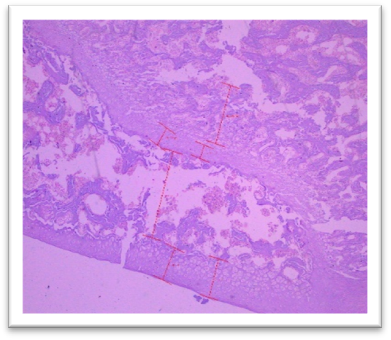

Histomorphometry

At the end of the study, femur bones were dissected and fixed for histological analysis. Group I (Normal) showed normal bone architecture, with well-organized chondrocytes. Group II (Lanthanum Carbonate only) maintained normal bone growth. Group III (Chronic Kidney Disease control) exhibited fibrocartilaginous changes, disorganized collagen, and impaired endochondral ossification, characteristic of Chronic Kidney Dosease. Groups IV (150 mg/kg), V (250 mg/kg), VI (500 mg/kg), and VII (750 mg/kg) demonstrated varying degrees of improvement in bone structure, with the highest dose (Group VII) showing the most significant restoration of normal bone architecture. Histomorphometry of bone: In Group III, designated as positive control for Chronic Kidney Disease, histomorphometric analysis of femur revealed significant fibrocartilaginous changes within the articular cartilage, characterized by an increased fibroblast, loss of chondrocyte organization, and disorganized collagen deposition. Furthermore, the growth plate exhibited a marked increase in the thickness of the hypertrophic zone, suggesting impaired endochondral ossification. Similar findings were observed by Saito et al. (2021) who observed that in Adenine-induced Chronic Kidney Disease, there was a reduction in bone minera density (BMD) throughout the body as well as in the femur Furthermore, micro- computed tomography (micro-CT) analysis revealed a decline in the microstructural integrity of the cortical bone, which contributed to diminished bone strength in both cortical and trabecular regions. Ferrari et al. (2014) reported that the bone microarchitecture in rats subjected to Adenine-induced renal failure exhibited significant alterations, characterized by a reduced trabecular number and an increased trabecular separation. Additionally, the presence of fibrosis was noted in the rats with Adenine-induced renal failure. Ni et al. (2018) performed a histomorphometry analysis and revealing that the bone mineral density (BMD) in the femurs of rats with Chronic Kidney Disease (CKD) was markedly lower than that observed in the control (CTL) group. Additionally, significant bone loss was evident in both cortical and trabecular bone parameters of the femurs.  Lanthanum Carbonate @150mg/kg, 250mg/kg, 500mg/kg and 750 mg/kg, histomorphometric analysis revealed very minimal to nearly absent fibroblast proliferation in the articular cartilage, characterized by the absence of fibroblast- like cells and well-maintained chondrocyte organization. Additionally, the growth plate exhibited moderate proliferation of the hypertrophic zone, indicating significant improvement in endochondral ossification compared to the positive control group (Group III) and lower-dose treatment groups. These findings suggest that the highest dose of Lanthanum Carbonate (750 mg/kg) may provide the most effective therapeutic benefits in mitigating bone-related pathological changes associated with Chronic Kidney Disease Yajima et al. (2018) demonstrated that Lanthanum Carbonate enhanced the mineralization of the periosteal surface, augmented bone mass within the intracortical resorption areas, and improved mineralization on the minimodeling surface at the endocortical region. They concluded that Lanthanum Carbonate has the potential to bolster cortical stability in patients with Chronic Kidney Disease (CKD)..

Fig. 27 Group IV Femur showing moderate fibroblastic changes at articular cartilage and moderate proliferation of hypertrophic zone under H & E 400X.

Fig. 28 Group V, Femur exhibited mild fibroblastic changes at articular cartilage and moderate proliferation of hypertrophic zone under H & E 400X.